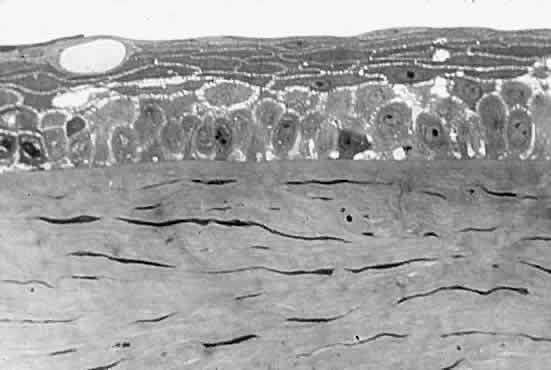

scattering increases and the cornea takes on a gray appearance (see Fig. 5).4 CORNEAL EPITHELIAL EDEMA In cases of advanced endothelial impairment or acute glaucoma, fluid collects

between the epithelial cells (Fig. 6). Fluctuations in the refractive index develop, and as the spaces between

the cells grow, the intensity of the scattering, or haze, grows. Potts

and Friedman5 have shown that in total corneal edema, the epithelial component accounts

for the greatest share of light scattering.  Fig. 6. Edematous epithelial layer of cornea as seen in a light micrograph. (Miller D, Benedek G: Intraocular Light Scattering. Springfield, IL, Charles

C Thomas, 1973. Courtesy of T. Kuwabara, Howe Laboratory, Harvard

Medical School) Fig. 6. Edematous epithelial layer of cornea as seen in a light micrograph. (Miller D, Benedek G: Intraocular Light Scattering. Springfield, IL, Charles

C Thomas, 1973. Courtesy of T. Kuwabara, Howe Laboratory, Harvard

Medical School)